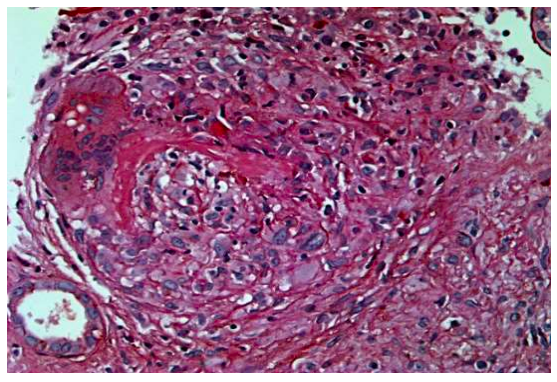

Aproximadamente 60 % dos glomérulos observados em uma biópsia renal estão afetados pela lesão ilustrada abaixo.

Este achado é mais compatível com qual contexto clínico?